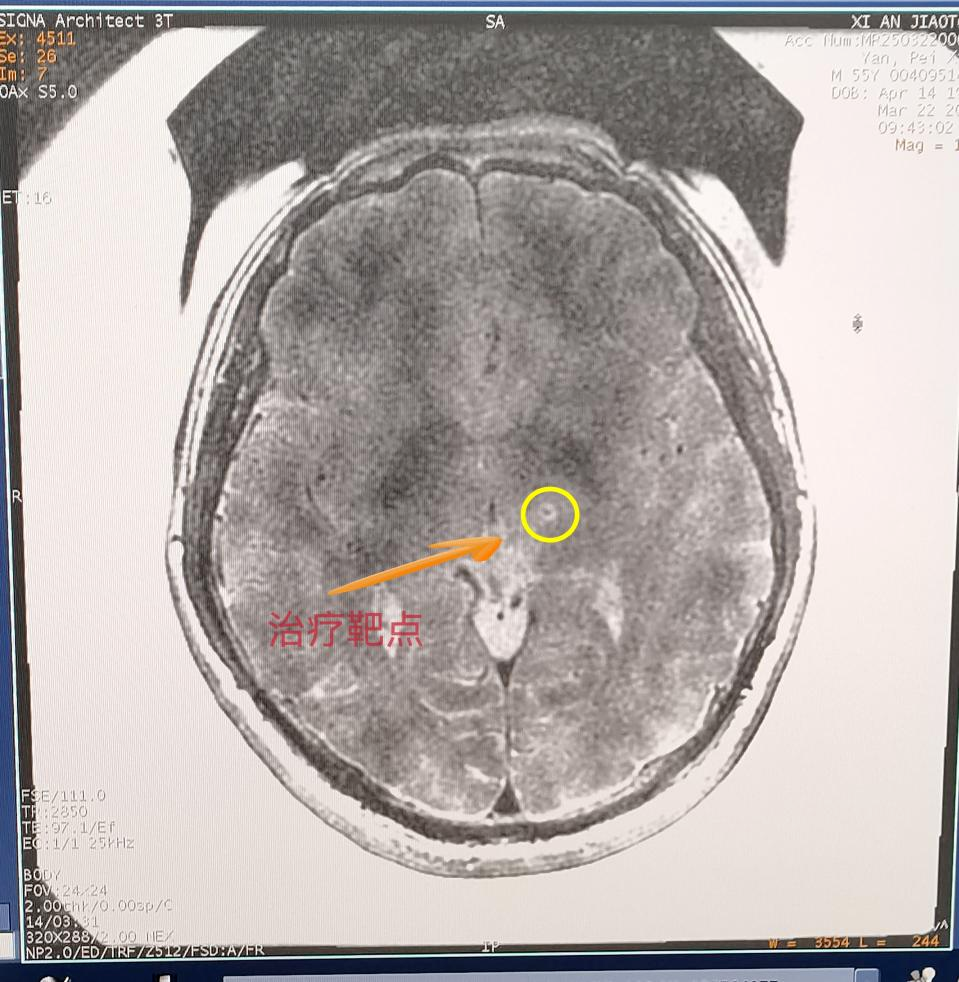

交大一附院神經(jīng)外科陳偉教授從病例出發(fā),詳細(xì)向大家講述了磁波刀技術(shù)原理,分享應(yīng)用案例并展示治療效果。

這項(xiàng)革命性技術(shù)融合了磁共振導(dǎo)航與聚焦超聲技術(shù),通過高精度磁共振鎖定腦內(nèi)異常神經(jīng)靶點(diǎn),運(yùn)用聚焦超聲波束穿透顱骨實(shí)施靶點(diǎn)高溫消融,從而阻斷震顫信號傳導(dǎo)。整個過程無需開顱,真正創(chuàng)造出“隔山打牛”的醫(yī)學(xué)奇跡。在治療過程中,閆先生在清醒狀態(tài)下躺入磁共振室,在醫(yī)生的嚴(yán)密監(jiān)護(hù)下,陳偉醫(yī)生通過最先進(jìn)的SIGNA Architect 3.0T磁共振系統(tǒng)鎖定閆先生腦內(nèi)異常神經(jīng)靶點(diǎn),運(yùn)用1024束精準(zhǔn)聚焦的超聲波穿過顱骨,精準(zhǔn)抵達(dá)大腦異常靶點(diǎn)。僅需15秒便讓震顫完全消失。這種無創(chuàng)、無痛的方式,不僅安全高效,還讓閆先生當(dāng)場感受到顯著改善。